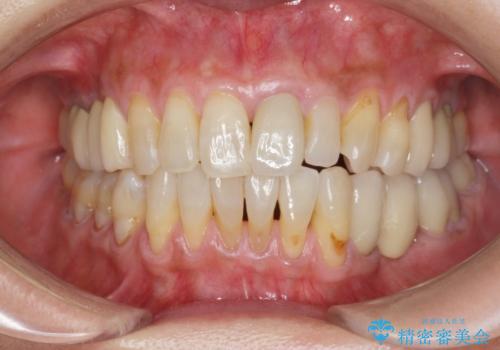

前歯の変色 セラミッククラウンによる審美回復

- 前歯の変色による審美障害の改善を希望され来院されました。

ジルコニアクラウンによる審美性の改善を計画します。

神経の治療をした歯は時間の経過と共に色調の変化が見られます。

このような際、ジルコニアクラウンを装着することで審美性の改善を達成することができます。